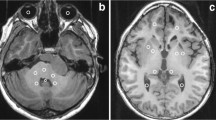

T1 map analysis

On a radiologic workstation (IntelliSpace Portal 10.0, Philips), a freehand tool was used to draw the respective ROI, as previously described in literature [22]. Mean pixel intensity, which equals the T1 relaxation time in milliseconds, was taken (Fig. 2). The following six regions were examined: nucleus caudatus (NC), putamen, GP, thalamus, ND, and frontal white matter (supplemental Figure 1). ROI with posttherapeutic lesions (e.g., resection cavities or gliosis) and disease-related alterations (e.g., demyelination or residual tumor) by employing conventional imaging sequences (T1 weighted, T2 weighted, diffusion weighted) were excluded from further analysis. Each region was measured bilaterally using the mean value, provided there was no pathology. All measurements were performed by two readers (D.G. and S.H.S. with 12 and 8 years of experience in pediatric brain MRI) in independent sessions in each of the two cerebral hemispheres of the patients. Measurements from both readers were employed for interobserver variability, and measurements from D.G. were used for further analysis.

T1 relaxation times in different brain regions in patients with a median of 4 gadobutrol administrations at timepoint 1 (green dots), 6 gadobutrol administrations at time point 2 (orange dots), and contrast agent–naive patients (black dots). Solid line: regression curve of the mean value of the normative cohort